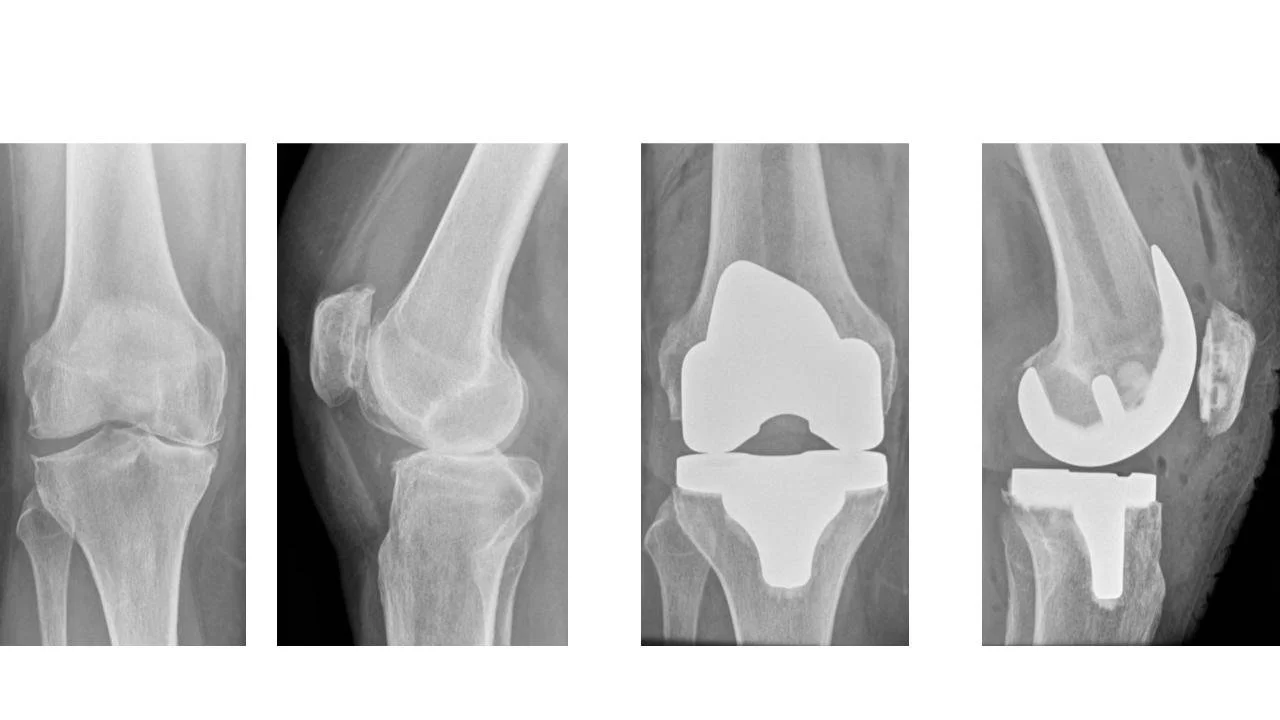

Attached below are a few examples of knee replacement x-rays taken before and after surgery. In these images, it may also be possible to appreciate the increasing complexity of the arthritis with bone destruction.

Example of total knee replacement for severe arthritis of the inside compartment (bowed knee). X-rays before and after surgery in both front and side views.